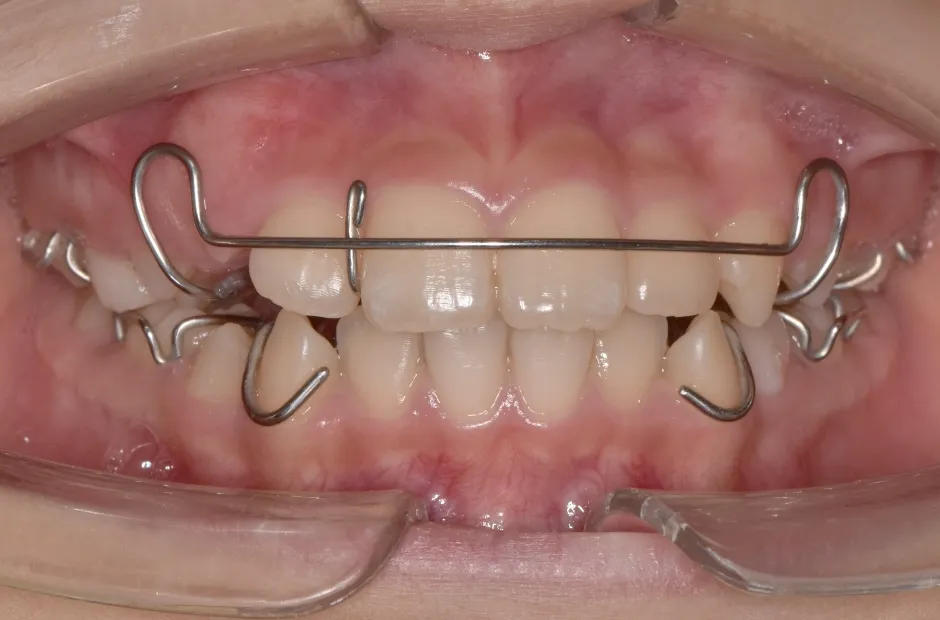

反対咬合

| 診断名・主訴 | 前歯反対咬合 |

|---|---|

| 年齢・性別 | 12歳・男性 |

| 治療期間・回数 | 1年半 18回 |

| 治療に用いた主な装置 | リンガルアーチ(前方誘導弾線) |

| 抜歯部位 | なし |

| 治療費 | 35万円(税抜) |

| リスク・副作用 | 装置による違和感・疼痛・歯肉退縮・歯根吸収・虫歯のリスクなど |

治療前

治療中

治療後